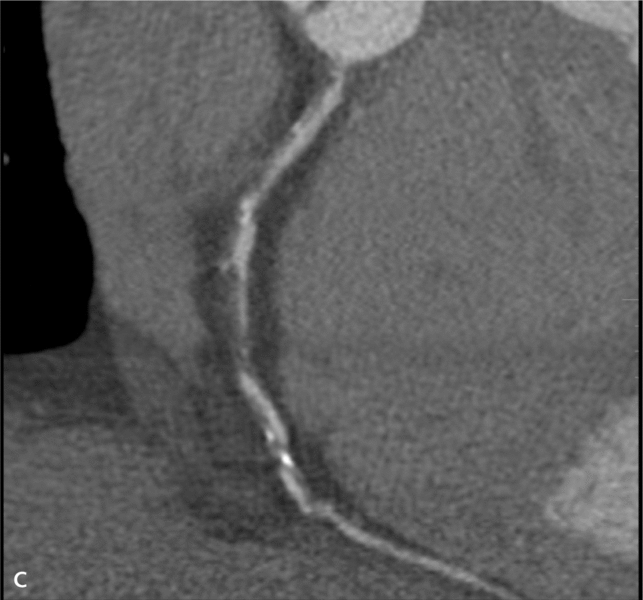

Mężczyzna, lat 68, z niecharakterystycznymi bólami w klatce piersiowej zgłosił się do specjalistycznej przychodni kardiologicznej. W wywiadzie rodzinnym podawał chorobę wieńcową w rodzinie, a osobniczym – nadciśnienie tętnicze i zwiększone stężenie cholesterolu. Wykonana próba wysiłkowa była niediagnostyczna (4,6 MET). Badanie echokardiograficzne nie wykazało istotnych nieprawidłowości. Badanie TK wykonane w trybie ambulatoryjnym uwidoczniło wielopoziomowe zmiany w prawej i lewej tętnicy wieńcowej (ryc. 1A), 50% zwężenie pnia lewej tętnicy wieńcowej z blaszką małej gęstości z remodelingiem dodatnim ściany naczynia (ryc. 1B) oraz niedrożność prawej tętnicy wieńcowej w segmencie 2/3 i wielopoziomowe zmiany w gałęzi diagonalnej i okalającej (ryc. 1C).

RYCINA 1. [A] Rekonstrukcja MIP Inversion. Niedrożność prawej tętnicy wieńcowej. [B] Rekonstrukcja MPR 2D – widoczne światło pnia lewej tętnicy wieńcowej (czerwona strzałka) oraz blaszka o niskiej gęstości powodująca bardzo dużego stopnia remodeling dodatni ściany naczynia (strzałka biała). [C] Rekonstrukcja MPR po krzywej wzdłuż osi długiej prawej tętnicy wieńcowej – wielopoziomowe zmiany niskiej gęstości z niedrożnością segmentu 2.